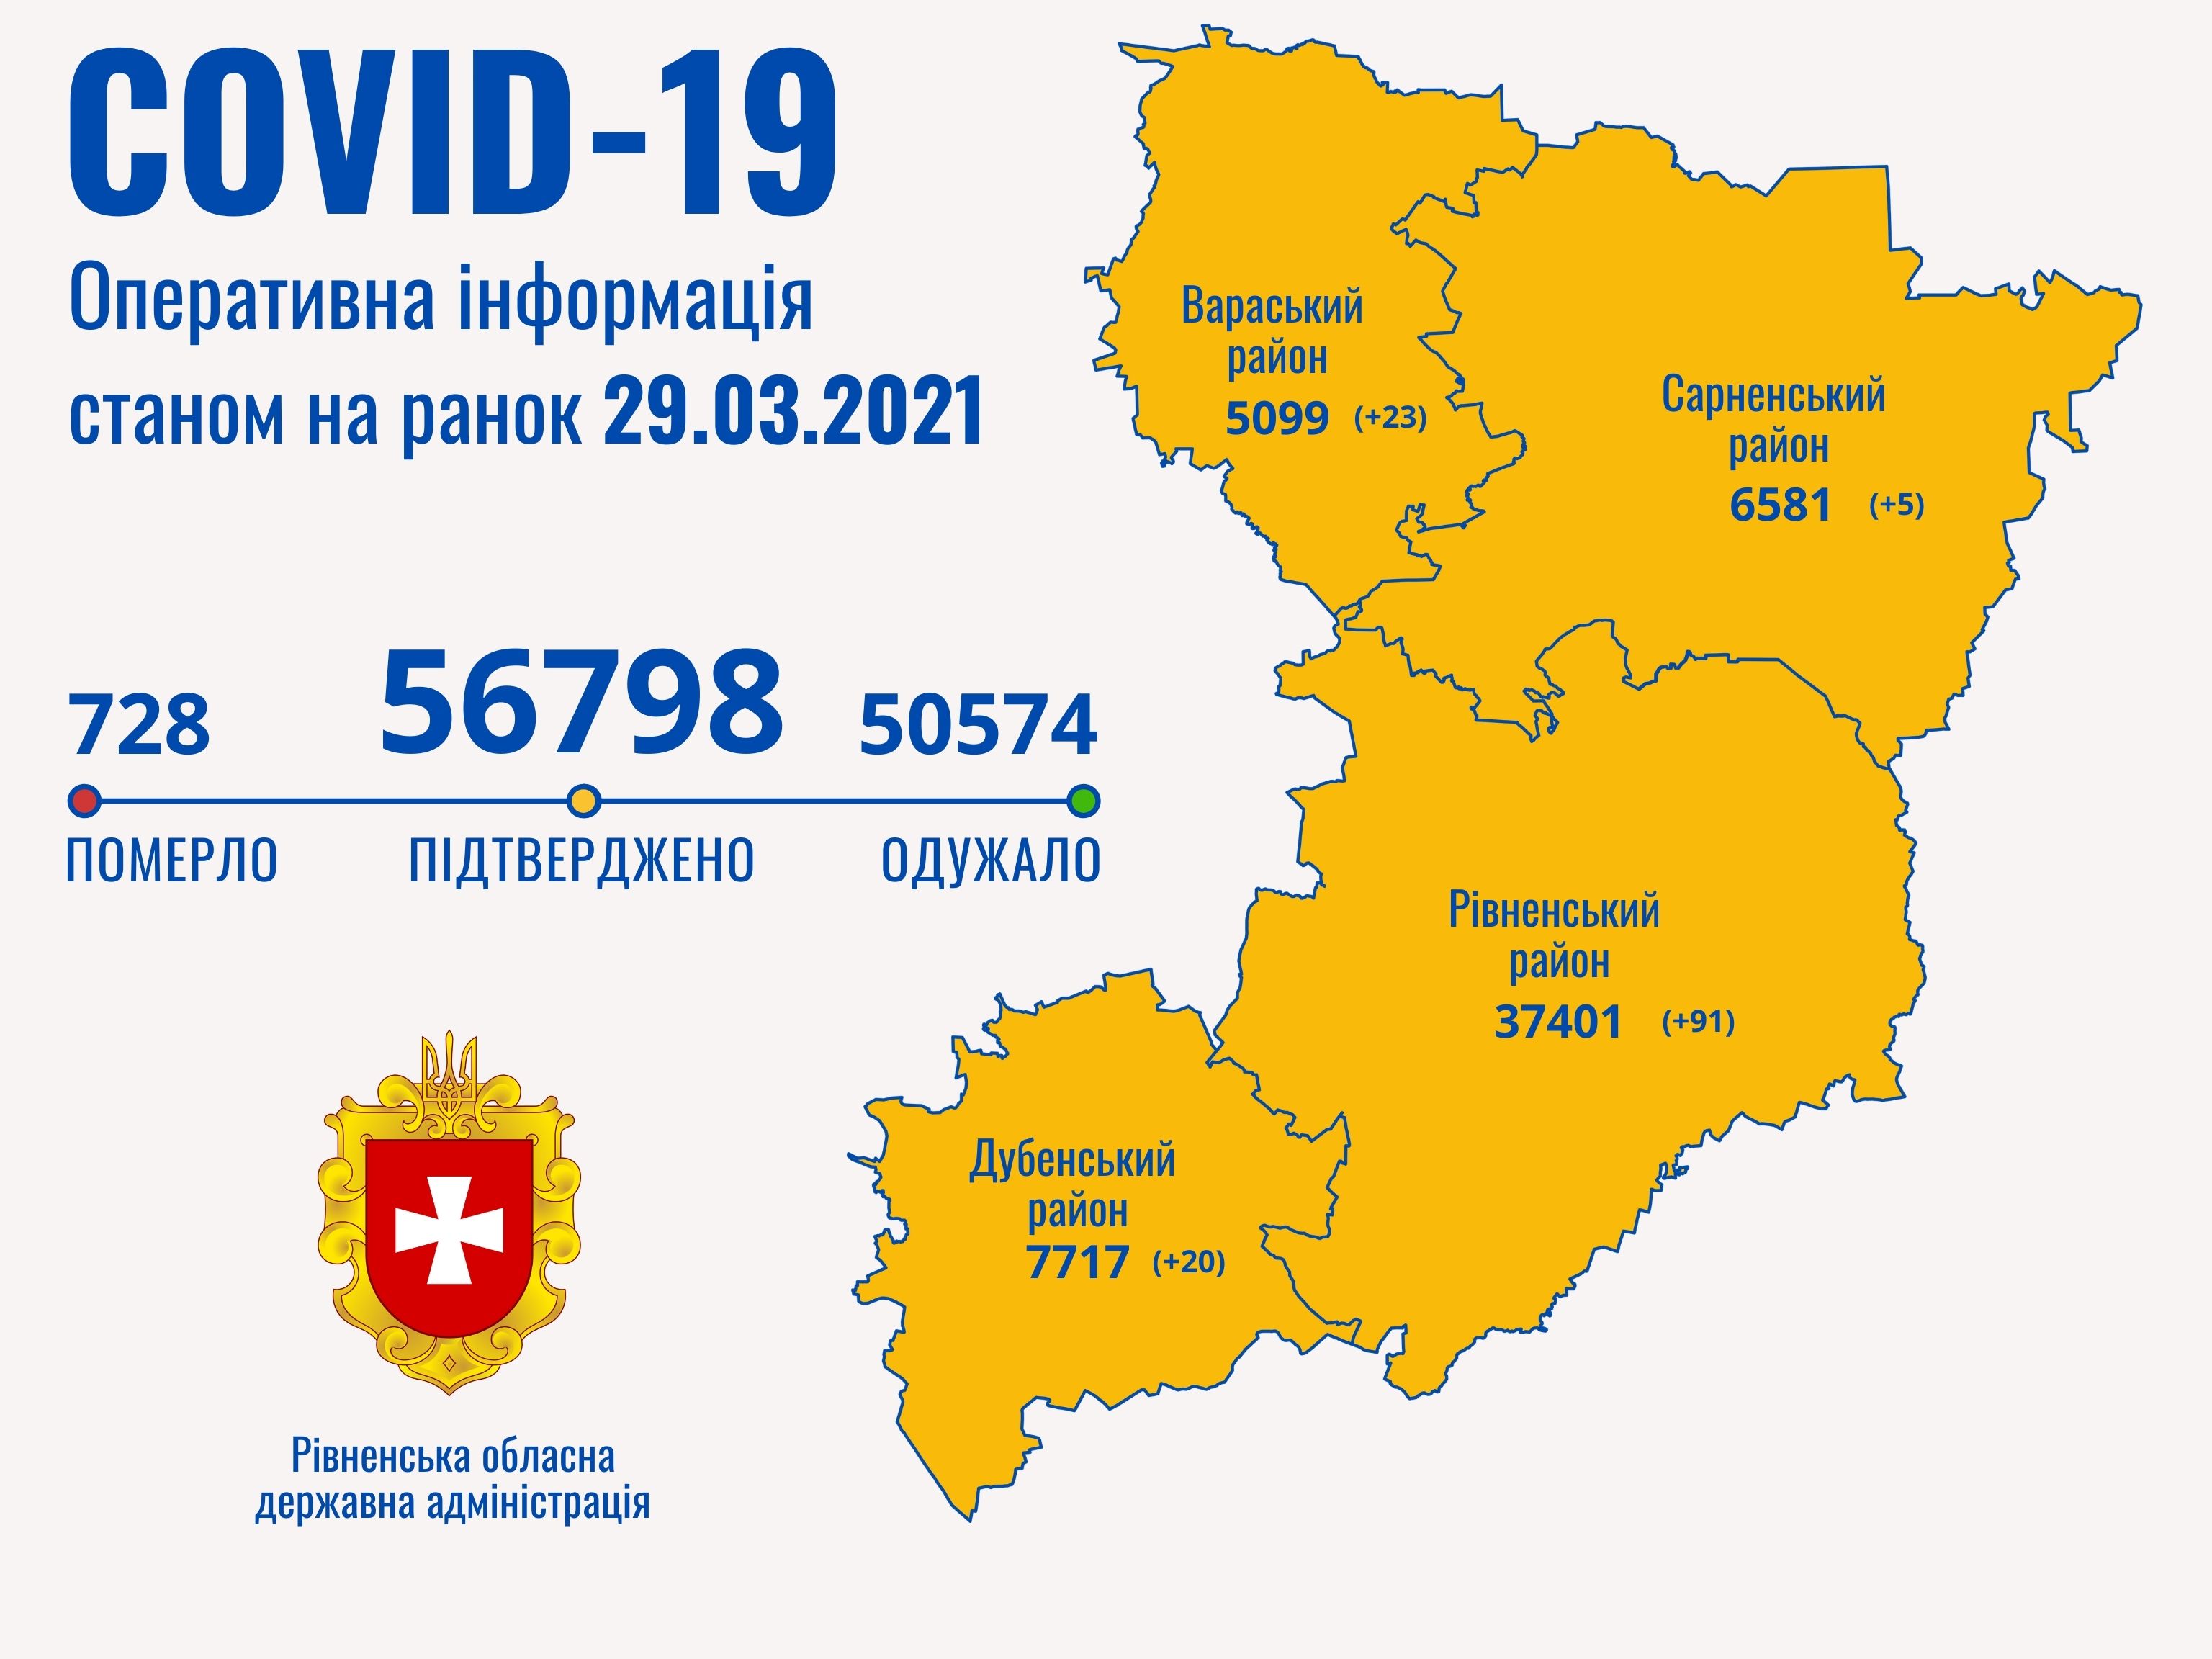

Пів тисячі - у важкому стані, 9 жителів Рівненщини померли за добу від коронавірусу

12.04.2021 10:17